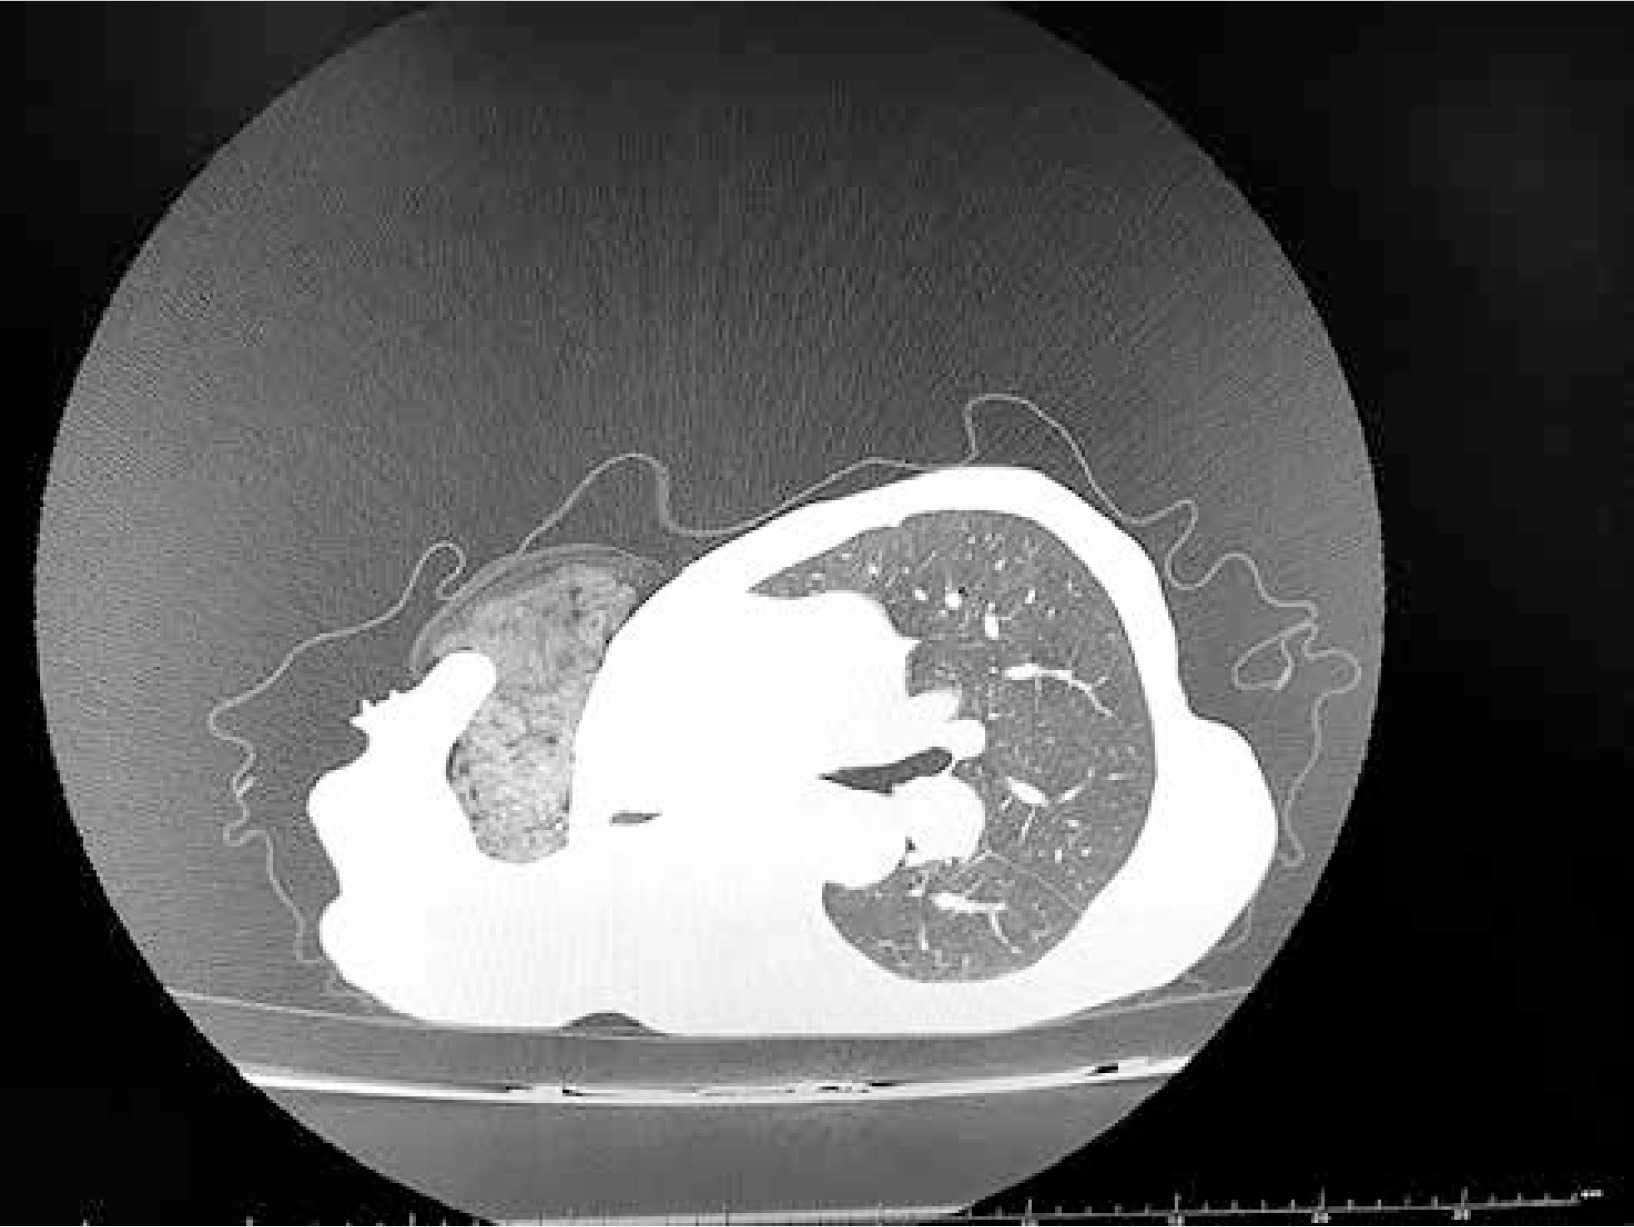

Figure 1

Computed tomography of the patient’s chest. Visible gauze dressing inside the pleural cavity (4.04.2017)